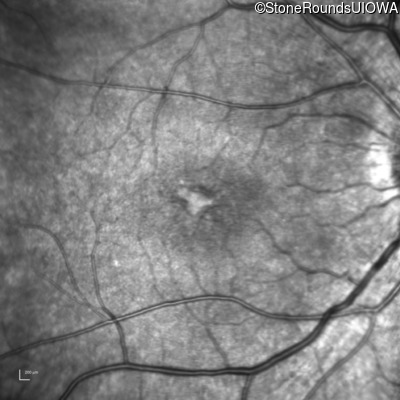

Infrared Fundus Photograph - Right - 20/32 -1

Exemplar